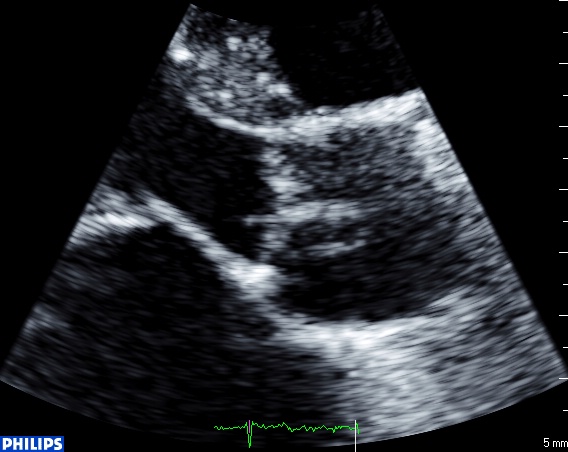

Dans la même semaine, deux vieilles dames en insuffisance cardiaque à prédominance droite, en fibrillation auriculaire chronique et présentant une HTAP importante ont des images échographiques étranges…

La premières sur la valve aortique : plusieurs éléments filamenteux, fins, mobiles, sur le versant ventriculaire et sur le versant aortique, sans le moindre contexte infectieux, et sans dysfonction de la valve.

En grand axe:

Le strand est défini comme un élément filamenteux, de moins de 1 mm d’épaisseur, plus généralement sur la valve mitrale que sur la valve aortique, plutôt sur le versant ventriculaire de la valve aortique et sur le versant auriculaire de la mitrale. Globalement, il semble qu’il y ait un lien entre la présence d’un stand et le risque d’Accident Vasculaire Cérébral chez le patient « tout venant ».